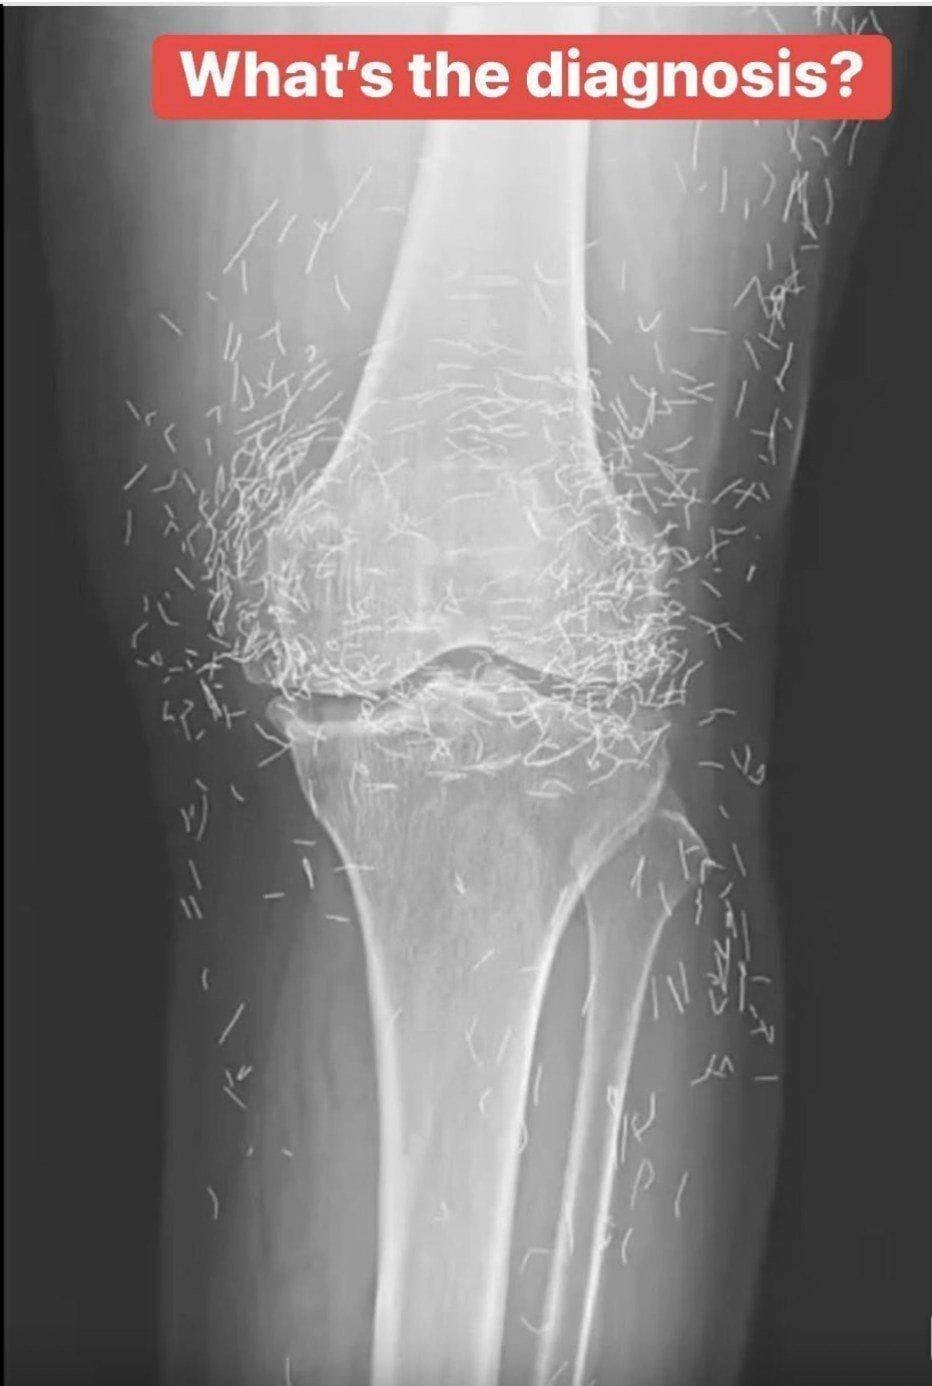

Years later, when doctors took X-rays to evaluate her knee condition, they weren’t prepared for what appeared on the images. Her knees were filled with dozens of bright, metallic flecks — tiny needles embedded deep within the joint area.

The findings were later documented in a case published by the New England Journal of Medicine.

Beyond inflammation, the needles created another problem: imaging complications. Metal objects can obscure parts of the anatomy on X-rays, making it harder for doctors to clearly assess joint damage or disease progression.